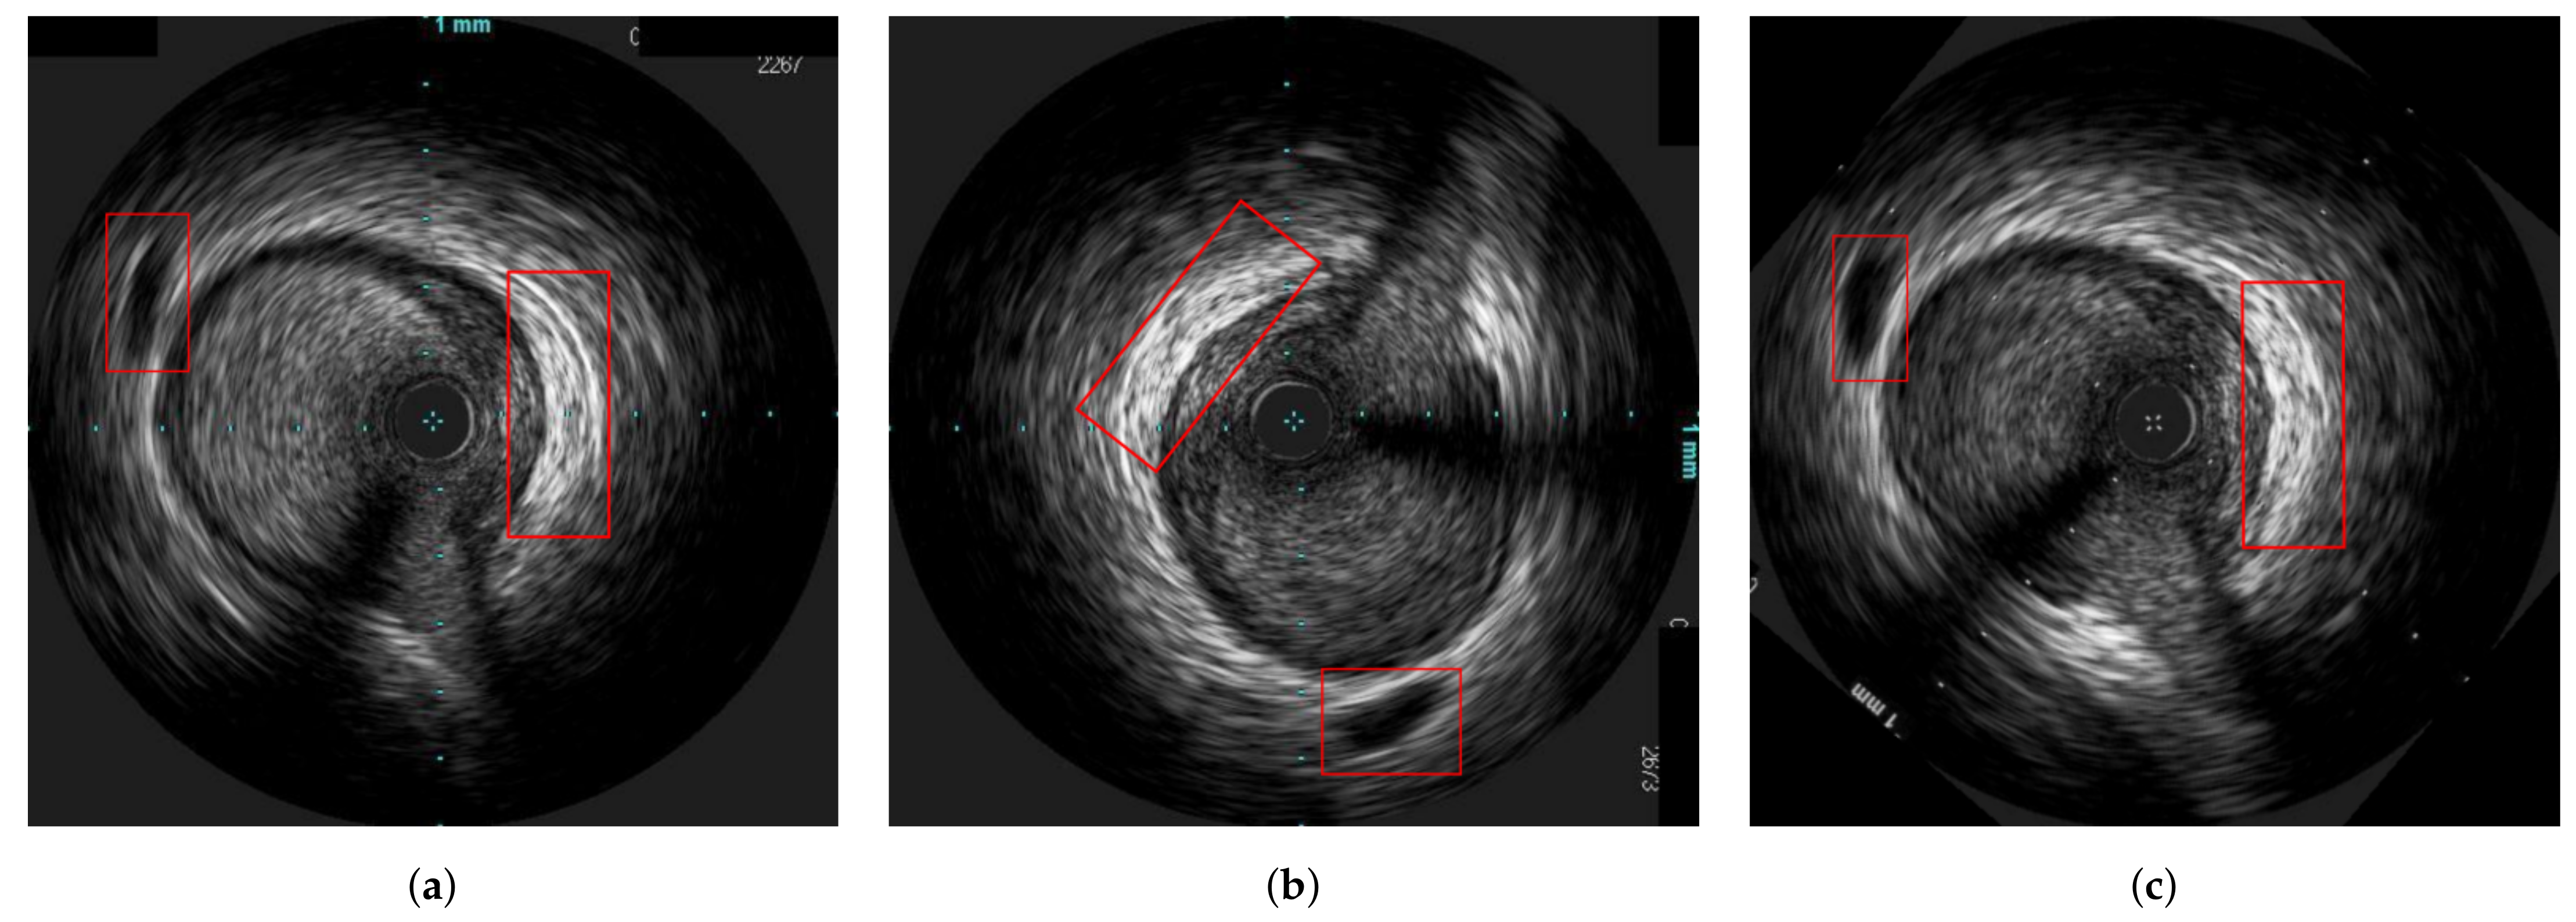

An example from a longitudinal registration (DTW algorithm) from one case on which the method performed very well is presented in Figure 7, while Figure 8 present the worst case among the dataset. We can observe that, although the maximum error for the patient 18 was 13 frames, its total number of frames was also twice the number of frames of patient 6 (i.e., ≈140 vs. ≈70), which made the longitudinal registration step more difficult and prone to error. In addition, the sagittal vessel views across each registration step of another case are shown at Figure 9. By observing the sagittal view of the unregistered pullbacks (Figure 9a), it becomes evident that the longitudinal registration step (Figure 9b) matched the corresponding vessel regions highlighted (with an orange eclipse) in the unregistered pair in Figure 9a. Although longitudinal correspondence was established, there was still a need to account for rotational inconsistencies and this was achieved in the axial registration step.

Figure 9. Sagittal vessel view corresponding to the (a) unregistered pullbacks (b) longitudinally registered pullbacks of patient 3. The left image of each subfigure corresponds to the pre-stent deployment pullback, and the right one to the post-stent deployment pullback. The red circles indicate the corresponding parts of the vesels.

In Figure 10, an explanatory result of the axial registration step following longitudinal registration for a pair of IVUS images of the two pullbacks is presented. Figure 10a,b present longitudinally registered frames of the first and second pullbacks of patient 6 (patient 18), respectively, while Figure 10c is the result of the axial registration between (a) and (b). Two other similar examples are depicted in Figure 11 and Figure 12. The result showed that the images were further aligned and the anatomical correspondence of the vessels structures was improved. The match was not perfect due to the existence of non-linear changes in the vessels such as extension of the vessel after stent deployment or increase of the size of the plaque, which could not be fully aligned with rigid registration techniques. Another reason is that the end-diastolic matched pairs may not depict exactly the same area, but rather neighboring ones. The reason for using rigid registration was because we wanted to achieve an overall alignment of the frames without altering the actual shape of the vessel’s structures as a non-rigid deformation would do. To this end, the obtained results as highlighted in Figure 9, Figure 10, Figure 11 and Figure 12, demonstrated that the proposed registration framework was a fast and robust tool to establish a more intuitive comparison in temporal IVUS pairs.